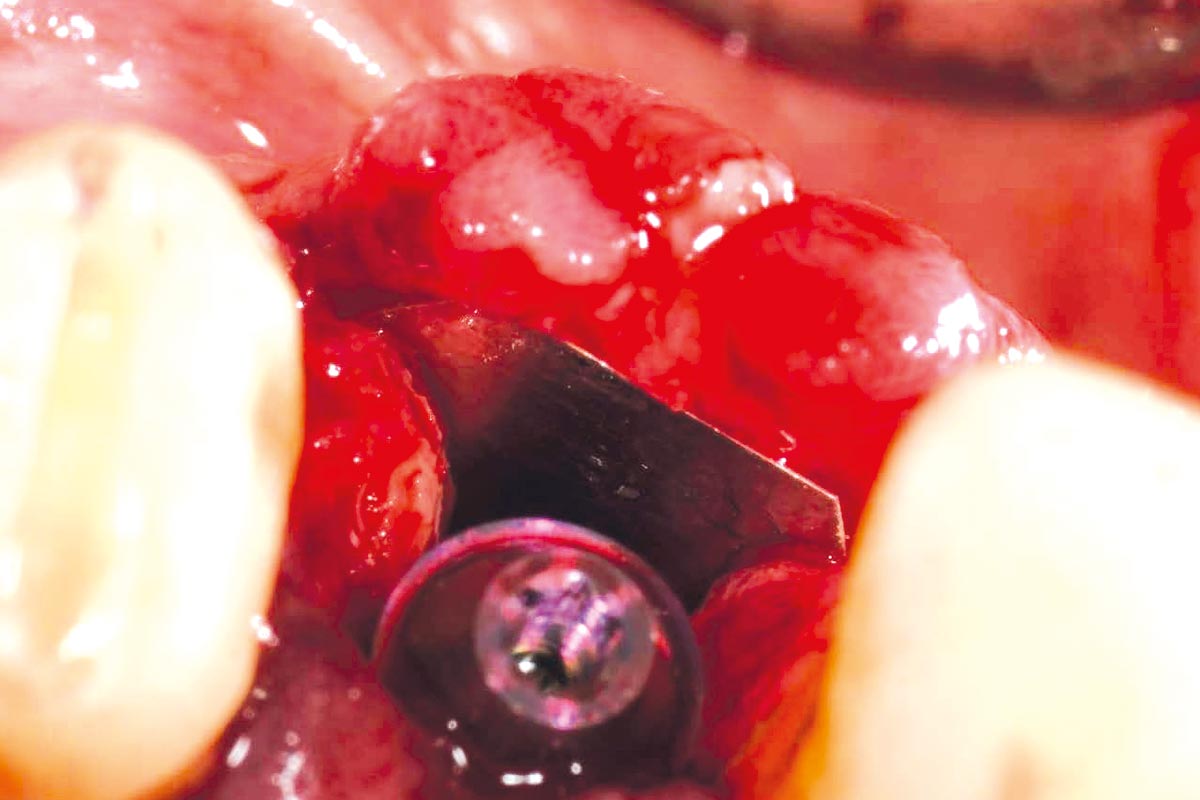

At the six-month re-entry, insufficient regeneration of the buccal plate was observed, compromising the available bone volume for implant placement. To address this deficiency, NOVAMag® SHIELD was introduced to reconstruct the buccal plate. Thus, an implant was placed followed by a membrane placement between the periosteum and the remaining buccal bone without fixation. Additional bone augmentation was performed to facilitate guided bone regeneration.